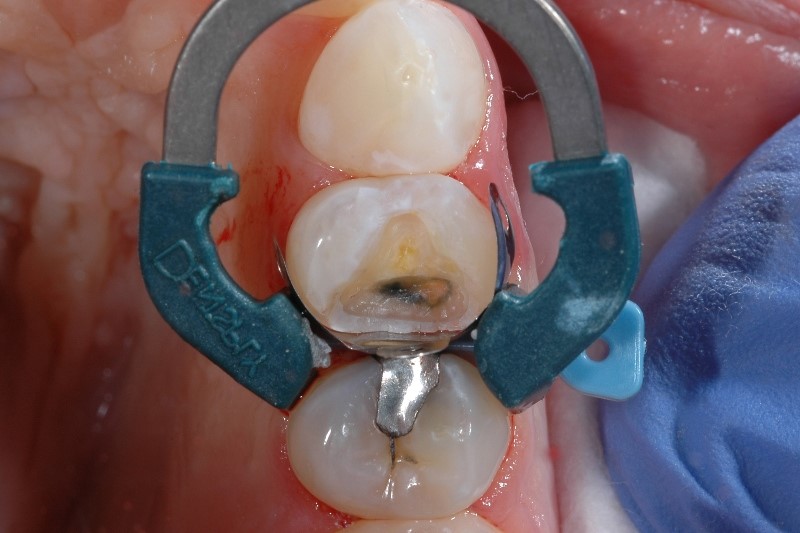

Überempfindlichkeit aufgrund von unzureichender Zahnisolation

Eine ordnungsgemäße Zahnisolation ist in jeder Phase einer Klasse-II-Restauration von entscheidender Bedeutung, denn dadurch wird Kontamination durch Speichel und Blut vermieden. Wenn der Restaurationsbereich kontaminiert ist, können die physikalischen Eigenschaften und somit auch der klinische Erfolg der Restauration beeinträchtigt werden, was sich bspw. durch postoperative Überempfindlichkeiten beim Patienten äußert.

Wie sich die Empfindlichkeit aufgrund von unzureichender Isolation vermeiden lässt

Probleme bei der Isolation sind keine Seltenheit. 97 Prozent der Behandler geben an, dass es in mindestens 1 von 10 Fällen schwierig ist, eine Klasse II Kavität adäquat zu isolieren.2 Neben den üblichen Maßnahmen zur Isolation sollten Sie auch die Bedeutung einer gut passenden Matrize berücksichtigen. Die Verwendung von speziell für die Platzierung von Kompositmaterialien entwickelten Matrizensystemen wie unser Palodent® V3-Teilmatrizensystem hilft dabei, eine dichte gingivale Versiegelung zu erzielen.